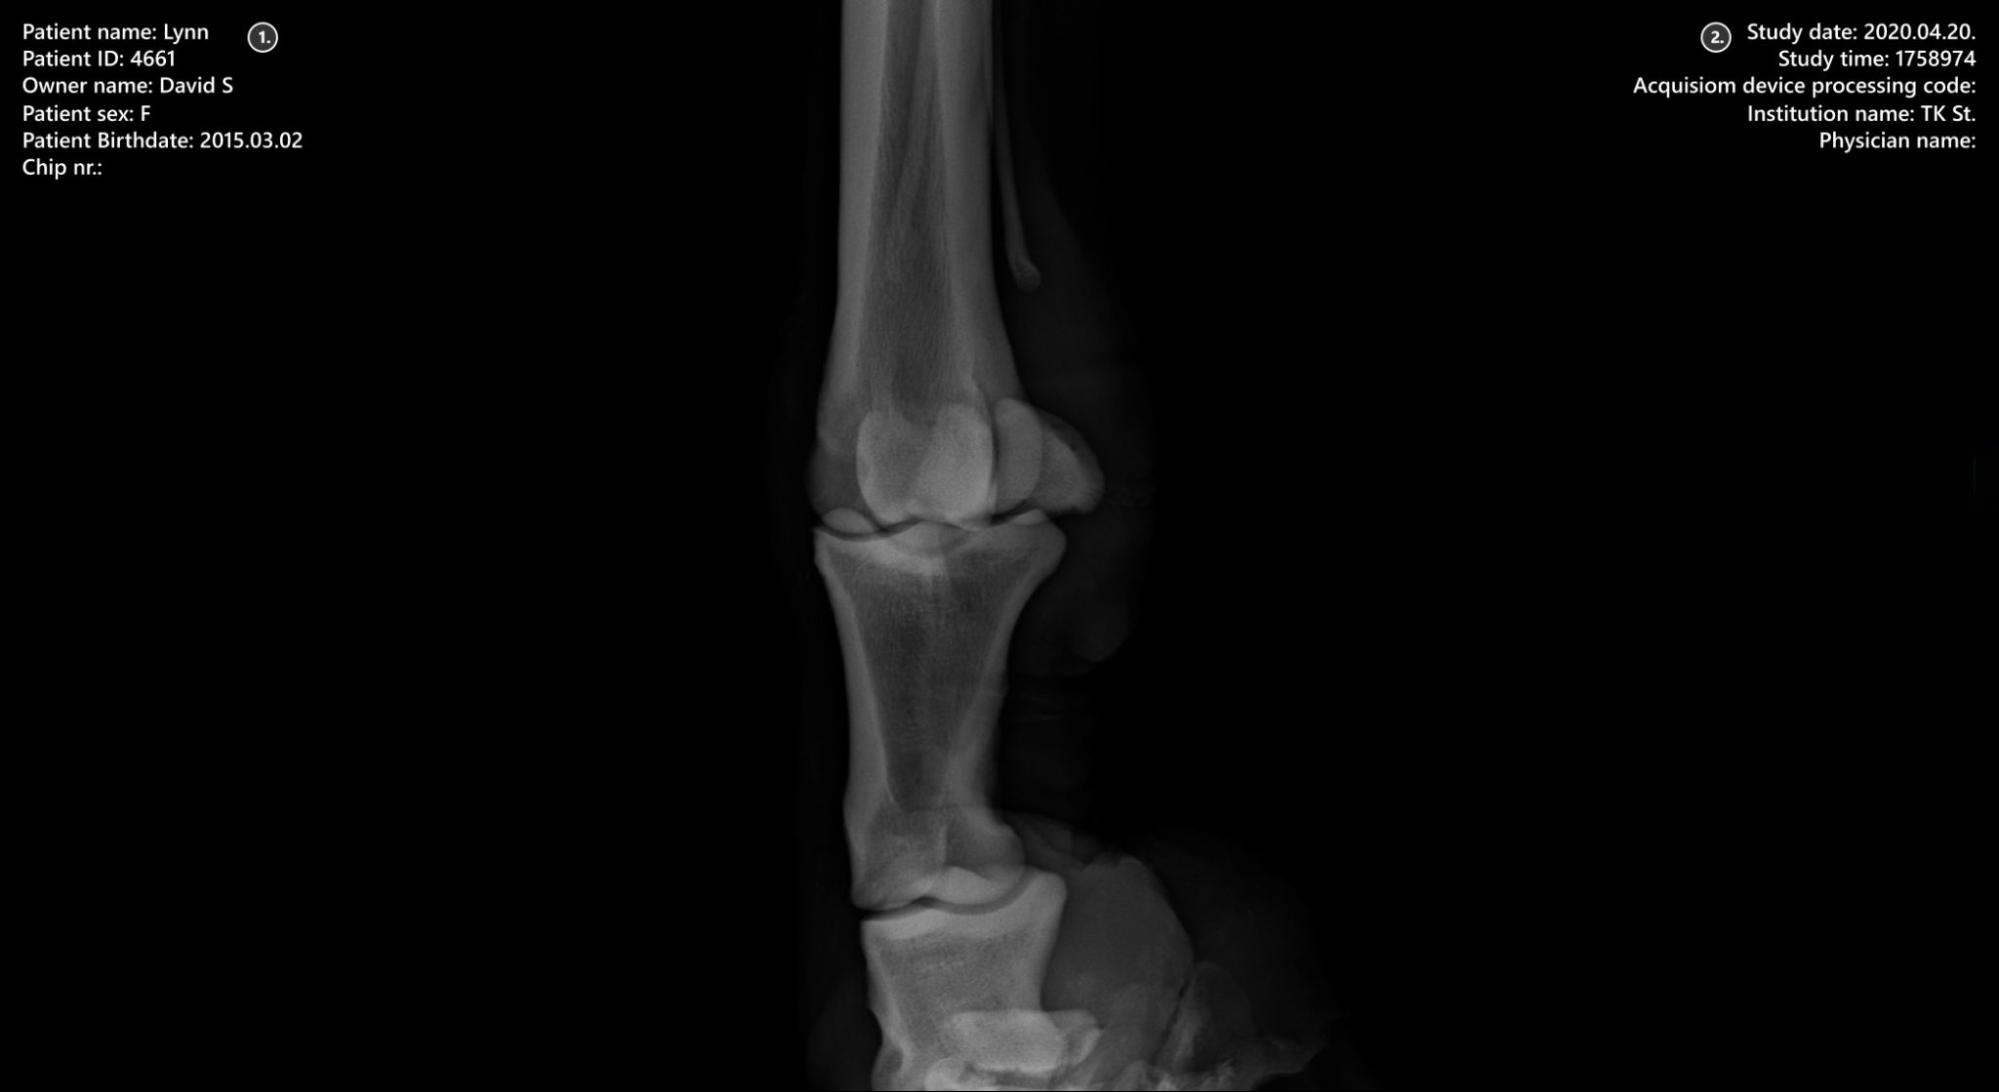

Megjelenítő felület¶

Beteginformáció

Tanulmányi információk